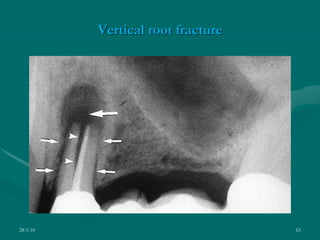

VERTICAL ROOT FRACTURE

28-1-10 63

Patients history

 H/o of trauma,

 seizure disorders,

 stroke,

 Miocardial infarction,

 Parafunctional habits

Clinical examination

 Crack probing

 Selective sensitivity by

bite tests

 Sinus tracts

 Dental operating

microscope

 Surgical exposure

 Illumination and dyes

28-1-10 64

28-1-10 65

Periodontal examination:

Narrow deep isolated pocket – probe movement from

side to side is restricted

Radiographic examination:

1.Halo like bone loss (J shaped lesion )

2.Isolated bone loss

3.Radiolucent space between the long axis of the material

and canal wall